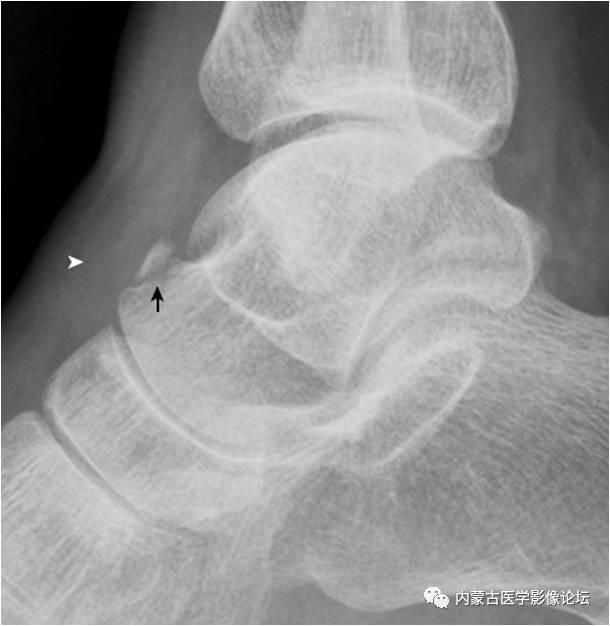

1.跟骨结节骨骺:形态多样,密度致密(箭),伴裂隙(箭头),为正常表现,勿误认为坏死。

2.Haglund外生骨疣与不典型骨刺:跟骨后上缘骨刺样突起(箭),属正常变异,称Haglund外生骨疣。穿高跟鞋时可损伤相邻的跟腱,形成Haglund综合征;跟骨结节下缘前突骨刺样突起(箭头),正常人可见,可无临床症状。